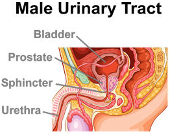

₦54,000.00Treat Frequent Urination, Urinary Tract Infections, Urine Leakage in Men caused by Prostate Enlargement.